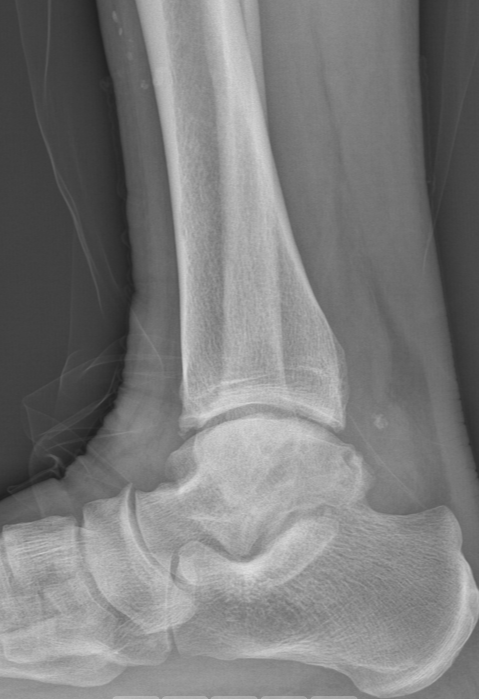

第一台手术的患者是位75岁的叔叔,被“脚脖子”痛缠了4年,疼得越来越厉害,病情已经到了严重阶段。

术前踝关节CT

术前后足力线X线

武勇主任团队给他做了3D打印导板辅助下人工全踝关节置换术。

这种手术适合踝关节病严重的患者,通过替换病变的关节结构,能帮着缓解疼痛、恢复关节活动,让老人日常走路更自在些。